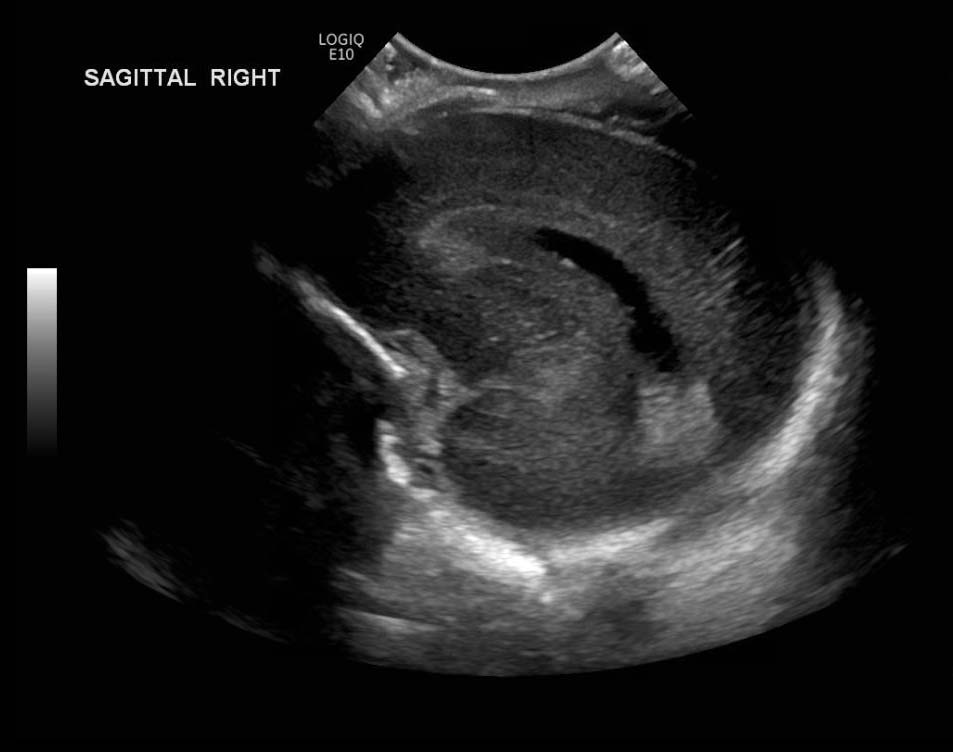

Age: 4 days (born at 24 weeks)

Sex: Male

Indication: Evaluate for germinal matrix hemorrhage

Grade 2 germinal matrix hemorrhage

Sample ReportLeft germinal matrix hemorrhage involving the caudothalamic groove and layering in the occipital horn of the left lateral ventricle without hydrocephalus (grade 2).

No abnormal brain parenchymal echogenicity or extra-axial collections.

Premature sulcation pattern.